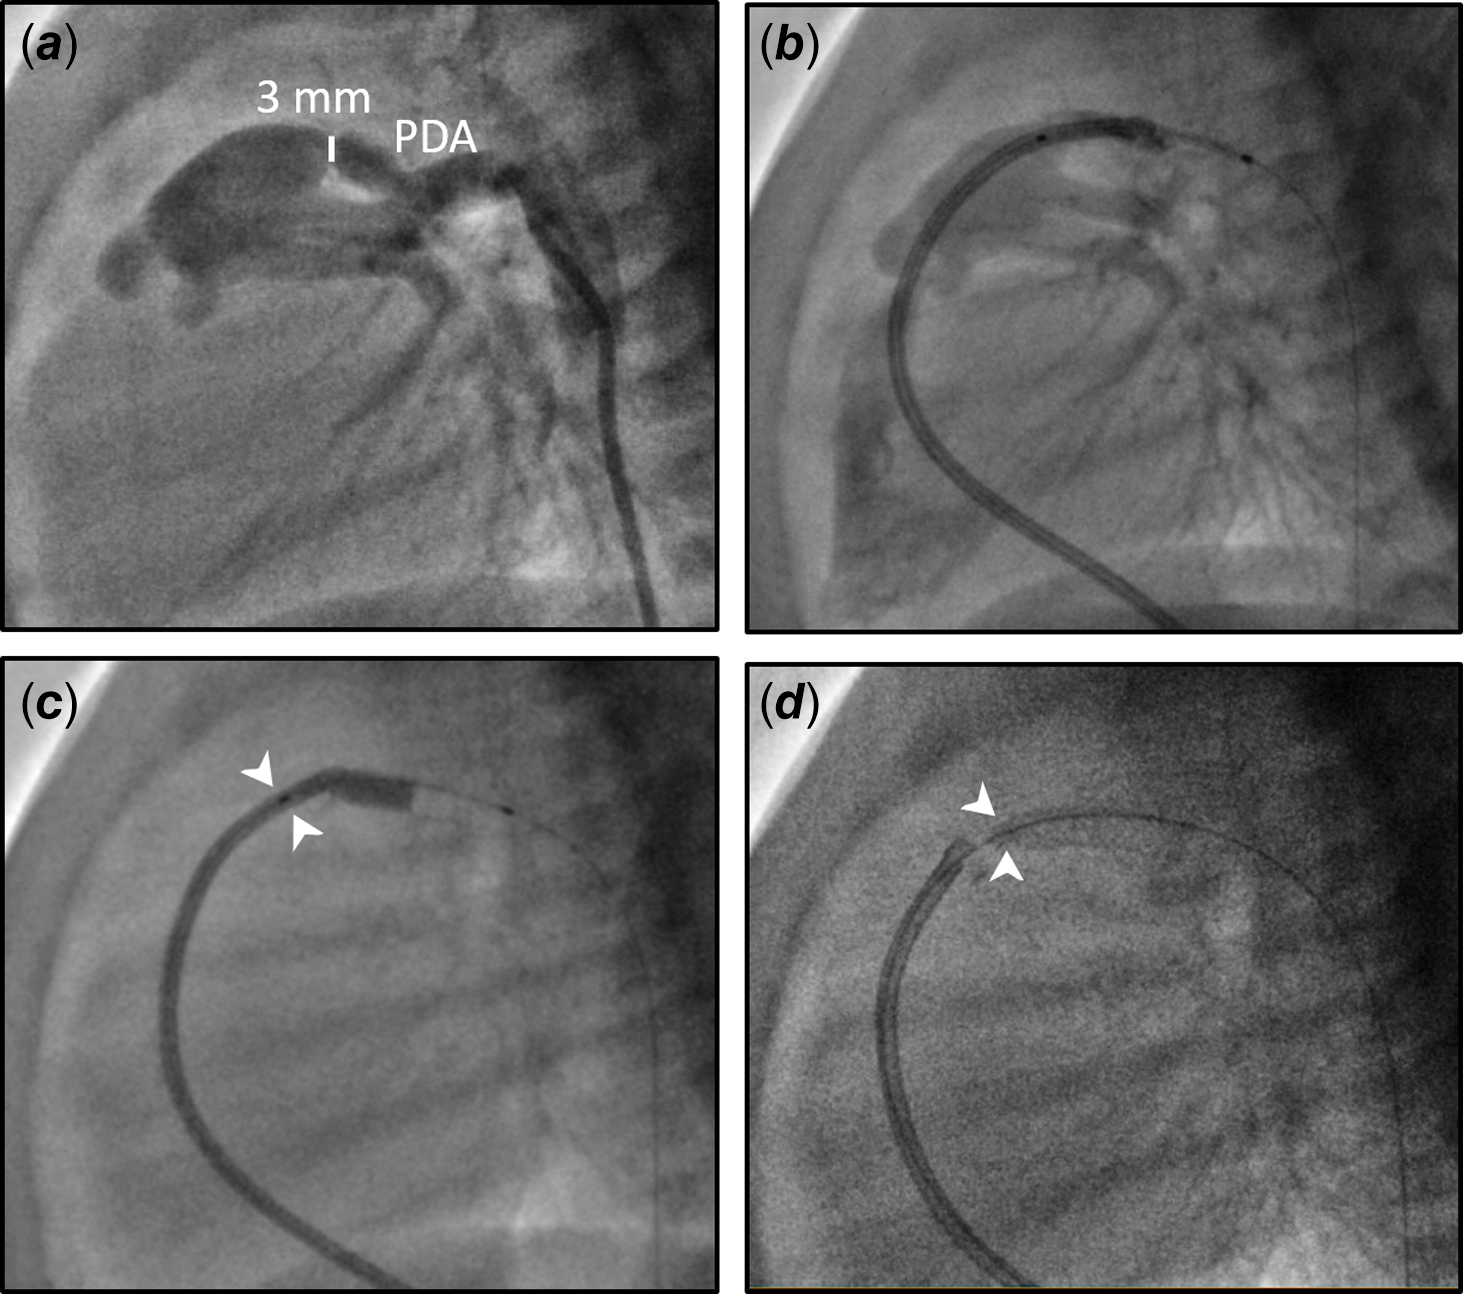

A twin male neonate was born at 36 weeks’ gestation with a birth weight of 2.5 kg. He was prenatally diagnosed with pulmonary atresia and intact ventricular septum. Due to prostaglandin shortage, we recommended trans-catheter interventions on the first day of life. A cardiac catheterisation was performed via accesses from the right femoral vein and left femoral artery. A right ventricular angiogram showed severely hypoplastic right ventricle including severely narrow infundibulum and no evidence of coronary sinusoids (Fig. 1). Therefore, radiofrequency perforation of the pulmonary valve and balloon valvuloplasty were performed successfully using a 6-mm VACS II at 5 atm (Video 1). The right ventricular systolic pressure reduced from 120 mmHg to 40 mmHg following the procedure, with a pressure gradient measured 30 mmHg between the right ventricular and pulmonary artery. Due to severe infundibular obstruction, we chose not to oversize the balloon (pulmonary valve annulus measuring 6.3 mm) to avoid iatrogenic valve regurgitation and proceeded with stenting of the patent ductus arteriosus to ensure a stable and sufficient source of pulmonary blood flow. Reference Aggarwal, Petit, Glatz, Goldstein and Qureshi1,Reference Promphan and Qureshi2 The patent ductus arteriosus is noted to be relatively straight, large, and arises from the proximal descending aorta. It would require a large stent from the arterial access which would have potentially led to pulmonary over circulation in a small infant. Reference Promphan and Qureshi2 To restrict flow across the ductal stent, we developed a novel technique with a plan to deploy from the venous access. We prepared a system including a 3.5-mm × 18-mm drug-eluting coronary stent over a wire which was housed in a 5F guide catheter. We advanced the system from the right femoral vein into the right atrium and ventricle, across the pulmonary valve, and crossing the patent ductus arteriosus into the descending aorta (Fig. 2). Approximately 1/3 of the stent and balloon were left inside the guide catheter while the balloon was inflated so that this stent portion would form a “funnel” and become a flow restrictor to the ductal stent (Video 2). The patient’s pulse oximetry was 90% on 30% FiO2 after the procedure, maintained adequate saturations during his hospital stay, and was discharged after 4 weeks. At his follow-up appointment at 11 months old, the patient was found to have severe pulmonary valve stenosis and the ductal stent became completely obstructed. He underwent a repeat balloon valvuloplasty at that time which resulted in mild to moderate pulmonary stenosis and regurgitation. He was doing well, was 2 years old at the time of this manuscript, without activity intolerance, and his pulse oximetry was 94% on room air.

Figure 2. Size and shape of the patent ductus arteriosus (PDA) and novel technique to create a flow restrictor. a: Lateral view of the PDA (smallest diameter 3 mm), b: stent over a wire was advanced in a 5 Fr guide catheter across the PDA, c: 1/3 of stent remained within guide catheter during balloon inflation (white arrowheads), d: distal ductal stent with a funnel acting as a flow restrictor (white arrowheads).